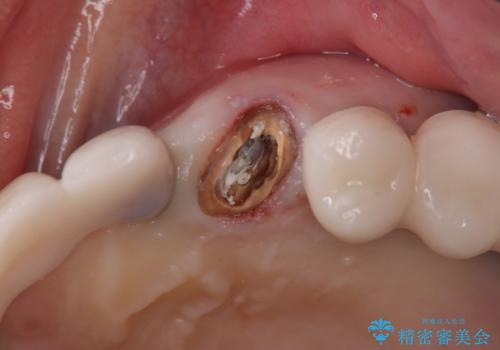

- 左上の歯肉は腫れてたまに膿が出るとの事で来院された患者様です。

検査を行い、抜歯即時インプラント(1Dayインプラント)治療を行いました。

抜歯をしインプラント埋入と骨補填材を填入して仮歯までを1日で行う「抜歯即時埋入即時過重」の手術をし、3ヶ月後には、オールセラミックを被せて定期検診となりました。